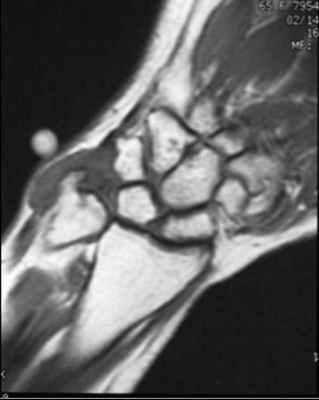

(Справа) МР-артрография в режиме Т1ВИ, коронарный срез, этот же пациент: визуализируется интактный тыльный пучок ЛПС. Разрыв мембранозной порции на данном срезе не виден (располагается кпереди). Разрыв центральной мембранозной порции ЛПС часто протекает бессимптомно. (Слева) Непрямая МР-артрография в режиме Т1ВИ FS с КУ, коронарный срез: визуализируется значительное расширение ладьевидно-полулунного промежутка. Отмечаются признаки артрита лучеладьевидного сустава. Головчатая кость смещена проксимально в промежуток между ладьевидной и полулунной костями. Картина характерна для ПЛПК запястья.

(Справа) МР-артрография в режиме PD FS, сагиттальный срез, этот же пациент: определяется разрыв восстановленного фрагмента связки, имеющего аморфную структуру и неровный контур. Полулунная кость отклонена в тыльную сторону, что позволяет заподозрить ТНПС. Положение полулунной кости должно быть сопоставлено с осью ладьевидной кости на соседних срезах.